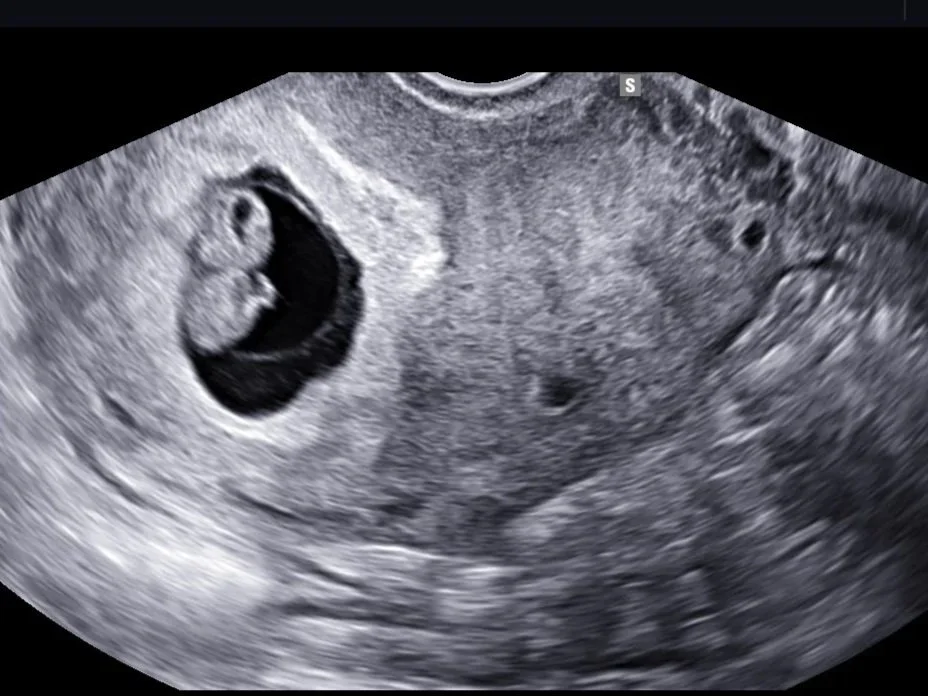

ultrakuva sikiöstä kahdeksannelta raskausviikolta, kaunis odotus

Viikon 8 lopulla olin varhaisultrassa (luulin itse silloin tosin että olin viikon 8 alussa tai korkeintaan puolessavälissä) Kauniissa odotuksessa. Ultra oli aamupäivällä, ja meillä oli samana iltapäivänä kaksivuotiaan synttärijuhlat, ja olin jo valmiiksi miettinyt, että voi perkele, jos uutiset onkin huonoja niin kiva pitää sit kulisseja yllä synttäreillä. Mutta onneksi uutiset olivat hyviä.

Siellä oli yksi vauvan alku, kädet alkoi jo muodostua, oikeassa paikassa ja oikean kokoinen. Oon kyllä ollut aika varma että siellä ollaan edelleen matkassa kun oireet on ollu niin jumalattoman hirveitä. Mutta mikä ihaninta, kätilö kertoi että on tullut jotain uusia raskauspahoinvointilääkkeitä! Pyydän ens viikolla neuvolasta niitä tai sitten soitan jo huomenna maanantaina terveysasemalle. Ahhh jos niistä sais avun ni se ois kyllä aivan best. Kerroin mun siskolle lapsen 2-v juhlissa. Ihasteltiin pojan kiharaa tukkaa ja sanoin vaan että tuleekohan seuraavalle samanlainen.